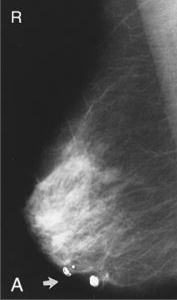

Καλοήθεις αποτιτανώσεις (εικόνα Α)

Δερματικού τύπου (είναι στρογγυλές)

Αγγειακού τύπου (είναι γραμμοειδείς tram track-line)

Δυστροφικού τύπου (αναπτύσσονται σε ουλώδη ιστό)

Εκκριτικού τύπου (αναπτύσσονται κατά μήκος των πόρων, είναι κυλινδρικές)

Λοβιακού τύπου (εντός της τελικής ανατομικής δομής του βοτρυδίου, είναι στρογγυλές, ελλειψοειδείς, ίσως σχηματίζουν ομάδες, μπορεί να είναι διάσπαρτες ή συρρέουσες)

Είναι λεπτές, πλειόμορφες, ανομοιογενείς ως προς την πυκνότητά τους και το σχήμα τους.